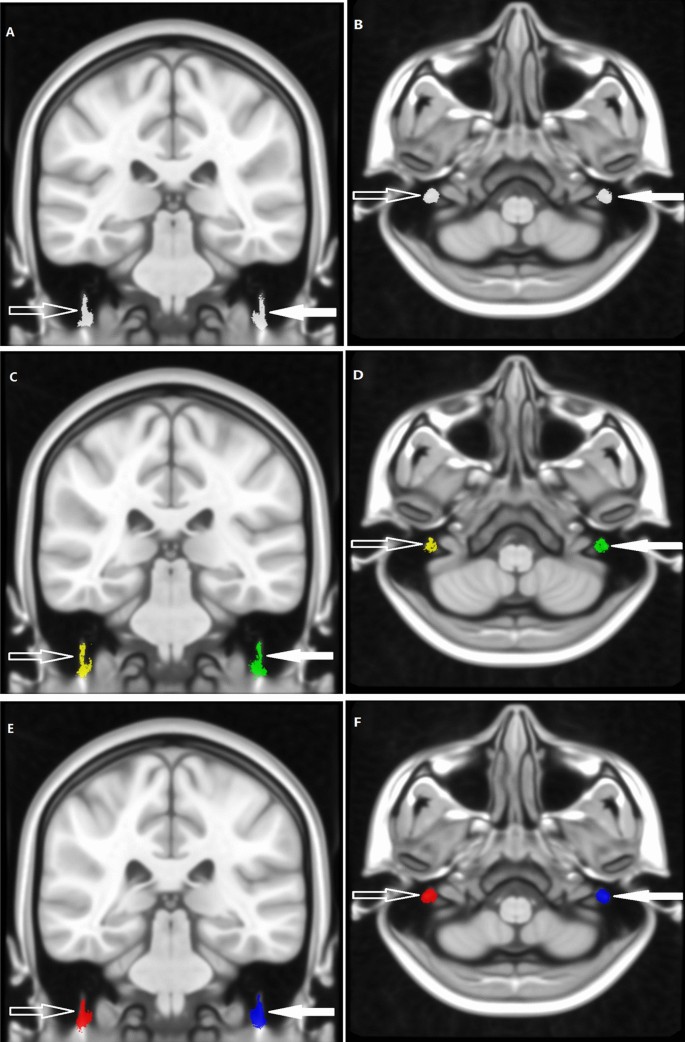

All results then were used to construct the maximum probability map (MPM), which assigned the most probable labels to each voxel according to the majority rule across subjects (Fig. 4). The indexes of DTI, named fractional anisotropy (FA), mean diffusivity (MD), axial diffusivity (AD), and radial diffusivity (RD), were calculated and extracted based on MPM.

According to the majority rule across subjects, the MPM of bilateral intratemporal facial nerves was constructed. The MPM of the healthy people (a, b), the patients (c, d), all people including the healthy people and patients (e, f). The left (solid arrow) and right (hollow arrow) intratemporal facial nerves were indicated by the arrows respectively.

In the present study, the MPM of 18 healthy people was named 18-Health-MPM, the MPM of 19 patients people was named 19-Patient-MPM, and the MPM of all 18 healthy people and 19 patients were named 37-All-MPM, respectively.

In this study, the raw RESOLVE data were resampled to 0.4 mm3 voxel size by performing affine transformation and nonlinear registration in the common MNI152_T1_0.4 mm space (Fig. 1). The resampled RESOLVE data were used to track the intratemporal facial nerve fibers of each subject in the 0.4 mm3 group-level common space, and the MPMs of the different group were obtained (Fig. 4). To observe the microscopic differences of intratemporal facial nerve fibers, the DTI indexes based on the different MPMs nerve were extracted.